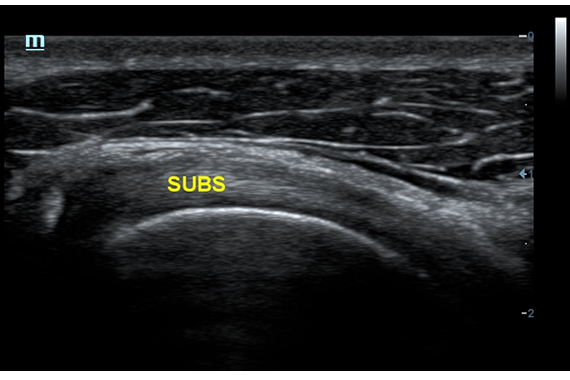

• Natural Touch Elastography - опция оценки эластичности ткани (эластография), с программой анализа. Действует на линейных датчиках 7L4A, L14-6NE и L9-3E